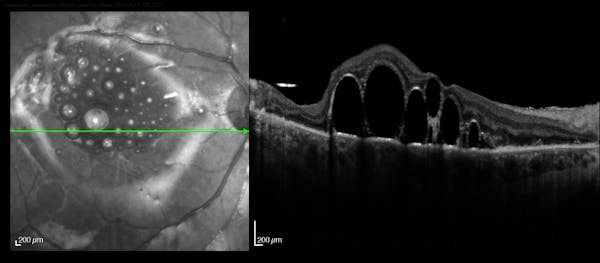

Slawomir Cisiecki, MD

Andre Gomes, MD